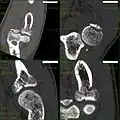

CT scan showing a radial head fracture -

Radial head fracture seen on 3D CT reconstruction